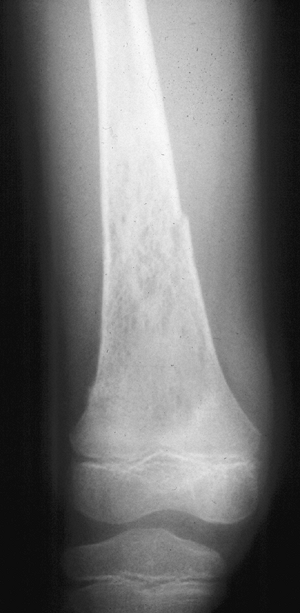

Figure 1-1 Pathologic fracture through unicameral bone cyst typically occurs without preceding pain.

Figure 1-2 Pathologic fracture through nonossifying fibroma typically occurs without preceding pain.

Figure 1-3 Pathologic fracture through an osteosarcoma is usually preceded by progressively worsening pain.P.9

Figure 1-4 Pathologic fracture through aggressive lesions such as this Ewing sarcoma is usually preceded by pain.

Figure 1-5 Pathologic fractures through giant cell tumors are usually preceded by pain, as was the case here.

Figure 1-6 Pathologic fractures through lesions created by metastatic carcinoma are often preceded by pain.-

Figure 1-7 Pathologic fractures through multiple myeloma lesions are often preceded by pain.

“No” implies a latent lesion without

progressive destruction. Most of these lesions can be diagnosed by

radiograph alone without biopsy. This situation is most common in the

pediatric population. Many of these fractures may be allowed to heal

before addressing the lesion itself, unless there is the potential for

deformity. -

“Yes” implies a potentially aggressive or

malignant lesion. These lesions usually require a biopsy to establish

the diagnosis. This situation includes most malignant primary bone

tumors and metastatic lesions.